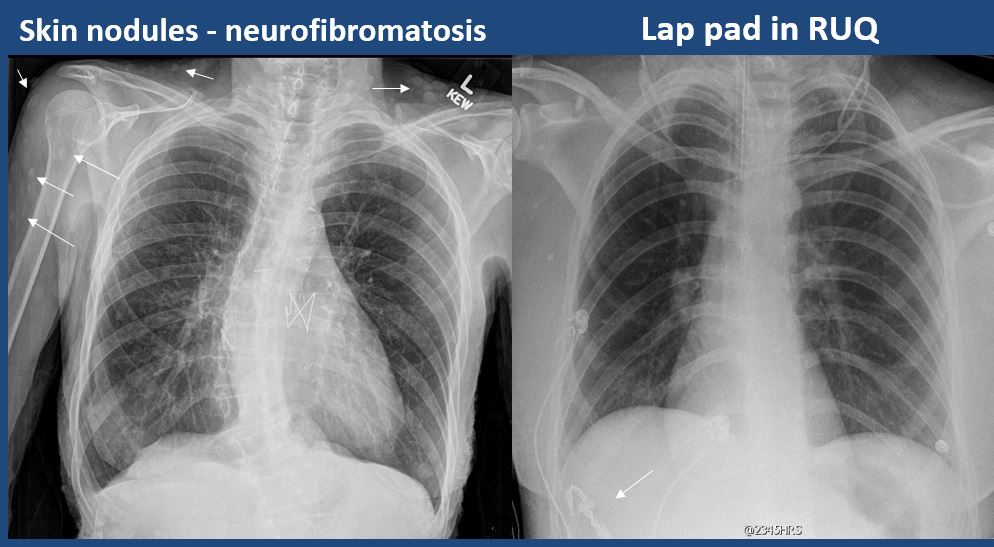

There is subcutaneous emphysema, focal or diffuse soft tissue abnormality, radiopaque foreign body, or post-surgical change or hardware. [Yes/No]

There are other devices such as an IABP, LVAD, vascular stents, cardiac valves, gastrostomy tube, other drains or tubes, anesthesia catheter, VP shunt, or neurostimulator present and improperly positioned. [Yes/No]

The bowel or organs of the upper abdomen are abnormal. [Yes/No]